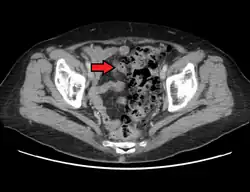

CT scan showing extensive diverticulosis of the sigmoid colon

• Contrast CT is the investigation of choice in acute episodes of diverticulitis and where complications exist.